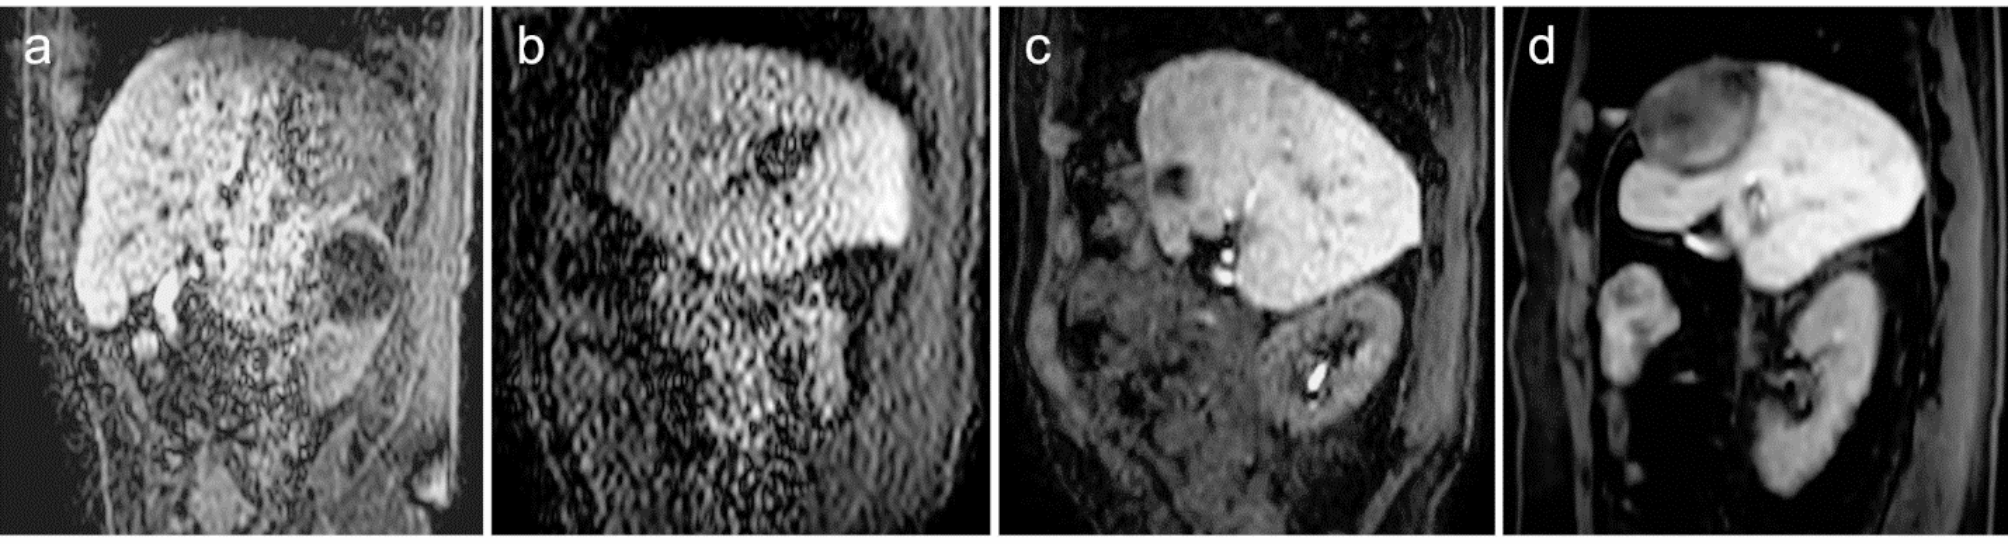

Fig. 4

Example of clinical cine-MRI with various visual scores. (a) cine-MRI with SENSE shows poor lesion conspicuity, excellent contrast enhancement, non-diagnostic image noise, good motion smoothness, and poor overall image quality. (b) cine-MRI with CS-no shows good lesion conspicuity, poor contrast enhancement, poor image noise, poor motion smoothness, and poor overall image quality. (c) cine-MRI with CS-strong shows good lesion conspicuity, good contrast enhancement, good image noise, excellent motion smoothness, and excellent overall image quality. (d) cine-MRI with CS-strong shows excellent lesion conspicuity, excellent contrast enhancement, excellent image noise, excellent motion smoothness, and excellent overall image quality.